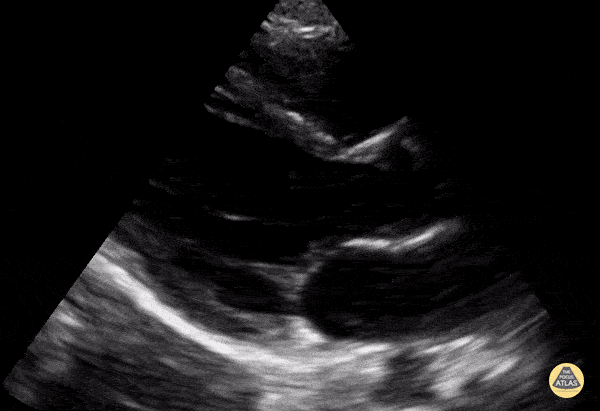

Normal PSLA in a 9-year-old. Contributor: Jaron Smith, MD, Phoenix Children's Hospital

View: Unspecified Parasternal Long Axis Parasternal Short Axis Apical Four-Chamber Subcostal Four-Chamber Subcostal Inferior Vena Cava Right Upper Quadrant Left Upper Quadrant Suprapubic Longitudinal Suprapubic Transverse Subxiphoid Anterior Thoracic Phrenic